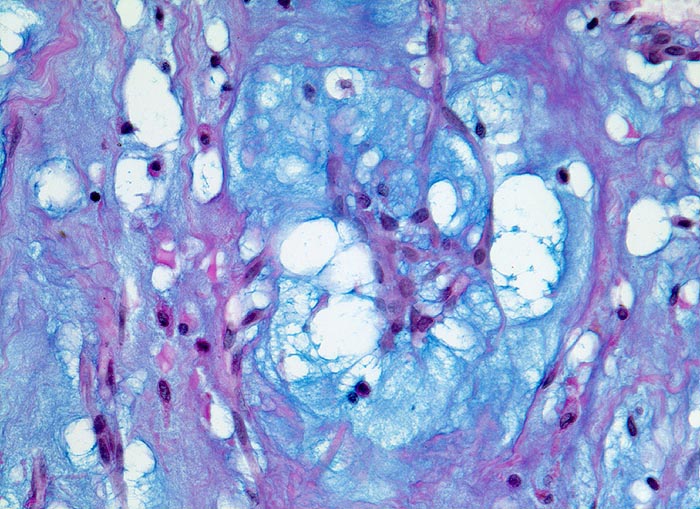

Vorhofmyxom

Makroskopie

Befund

Pathologischer Befund